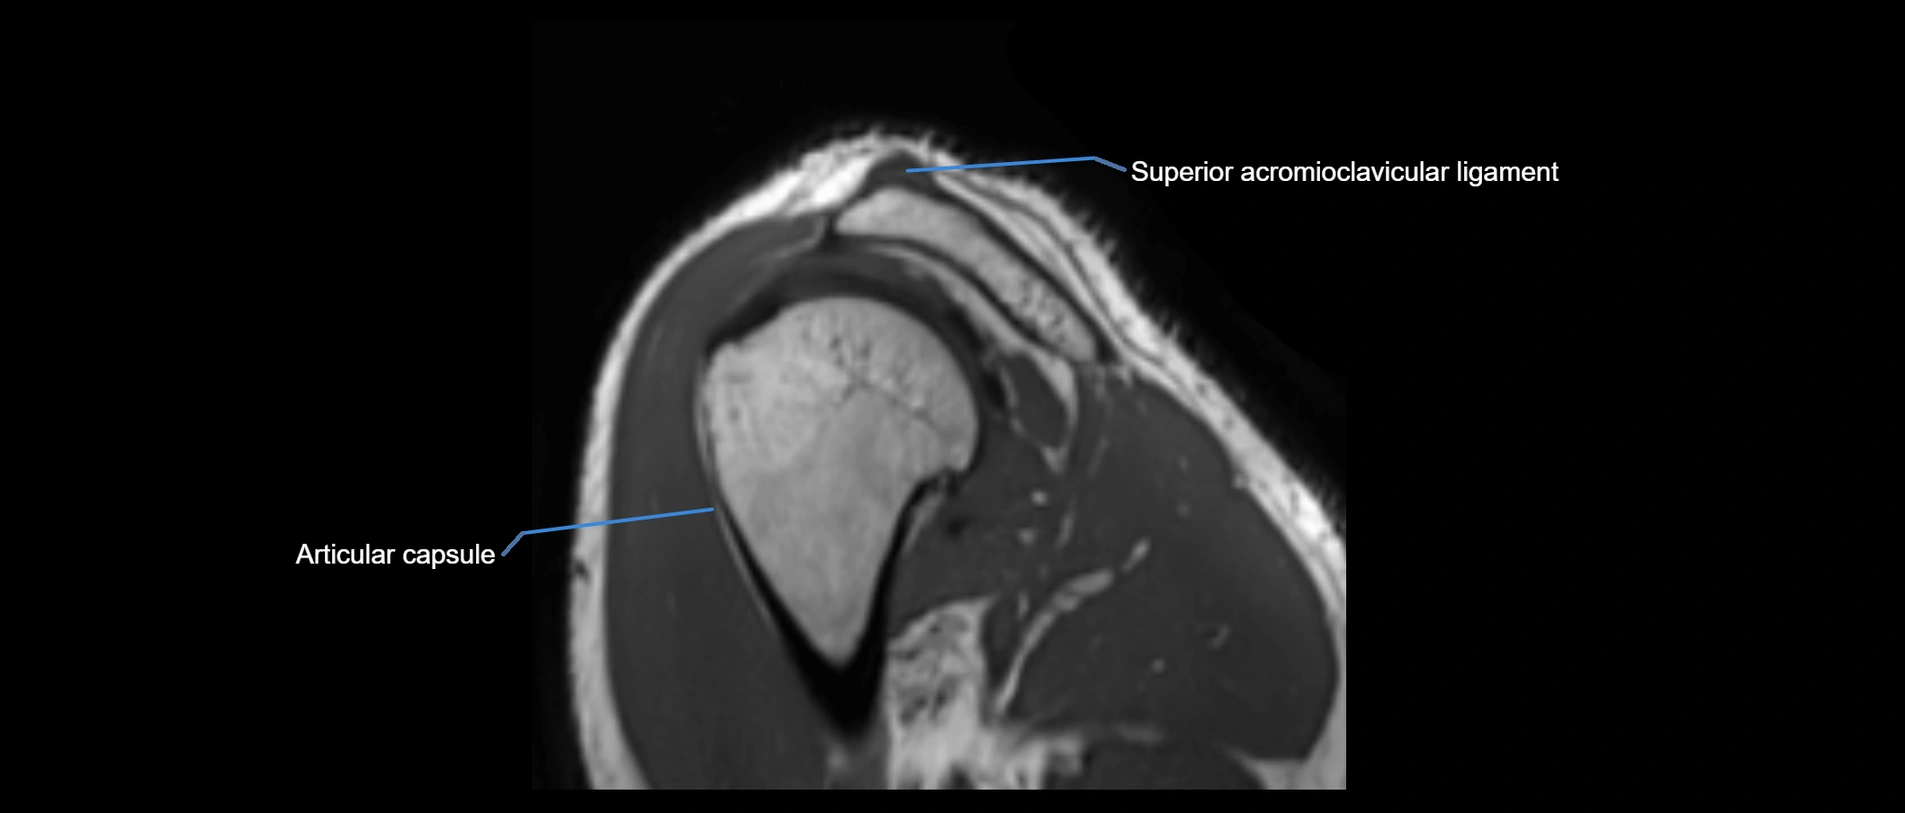

MRI Appearance

• T1-weighted images:

• Normal ligament: Low signal (dark linear band) spanning acromion to clavicle.

• Surrounding fat planes: Bright, delineating the ligament clearly.

• Marrow of clavicle and acromion: Bright due to fatty content.

• Tears: Discontinuity or irregular thickening with intermediate-to-bright signal.

• Chronic injury: Thinning, fraying, or irregular low-signal fibers with adjacent scarring.

• T2-weighted images:

• Normal ligament: Low signal, homogeneous.

• Partial tear or sprain: Focal hyperintensity or thickening.

• Complete tear: Discontinuity with fluid-bright gap between clavicle and acromion.

• Associated edema: Bright signal in distal clavicle or acromion marrow.

MRI images

image